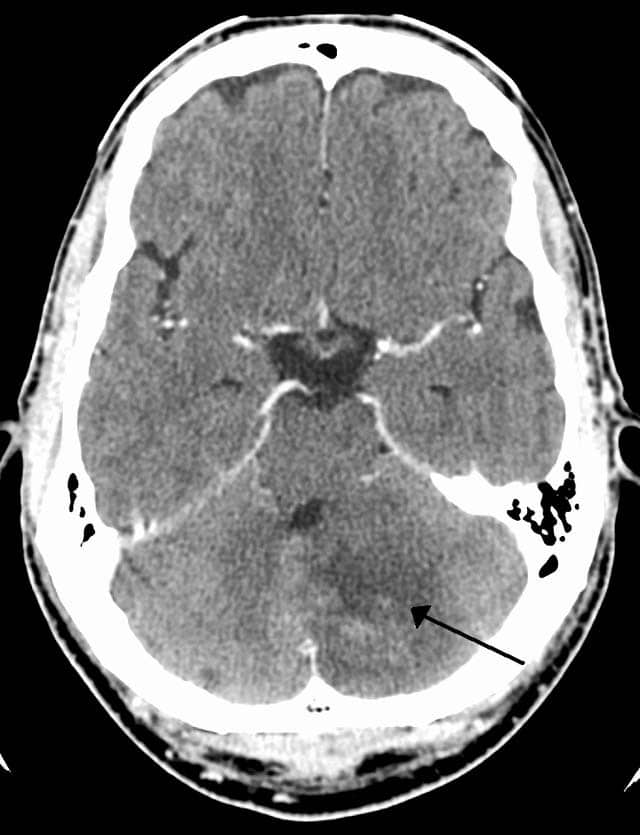

Fig 1.4 - CT scan of a left sided cerebellar stroke.

CT scan of a left sided cerebellar stroke.